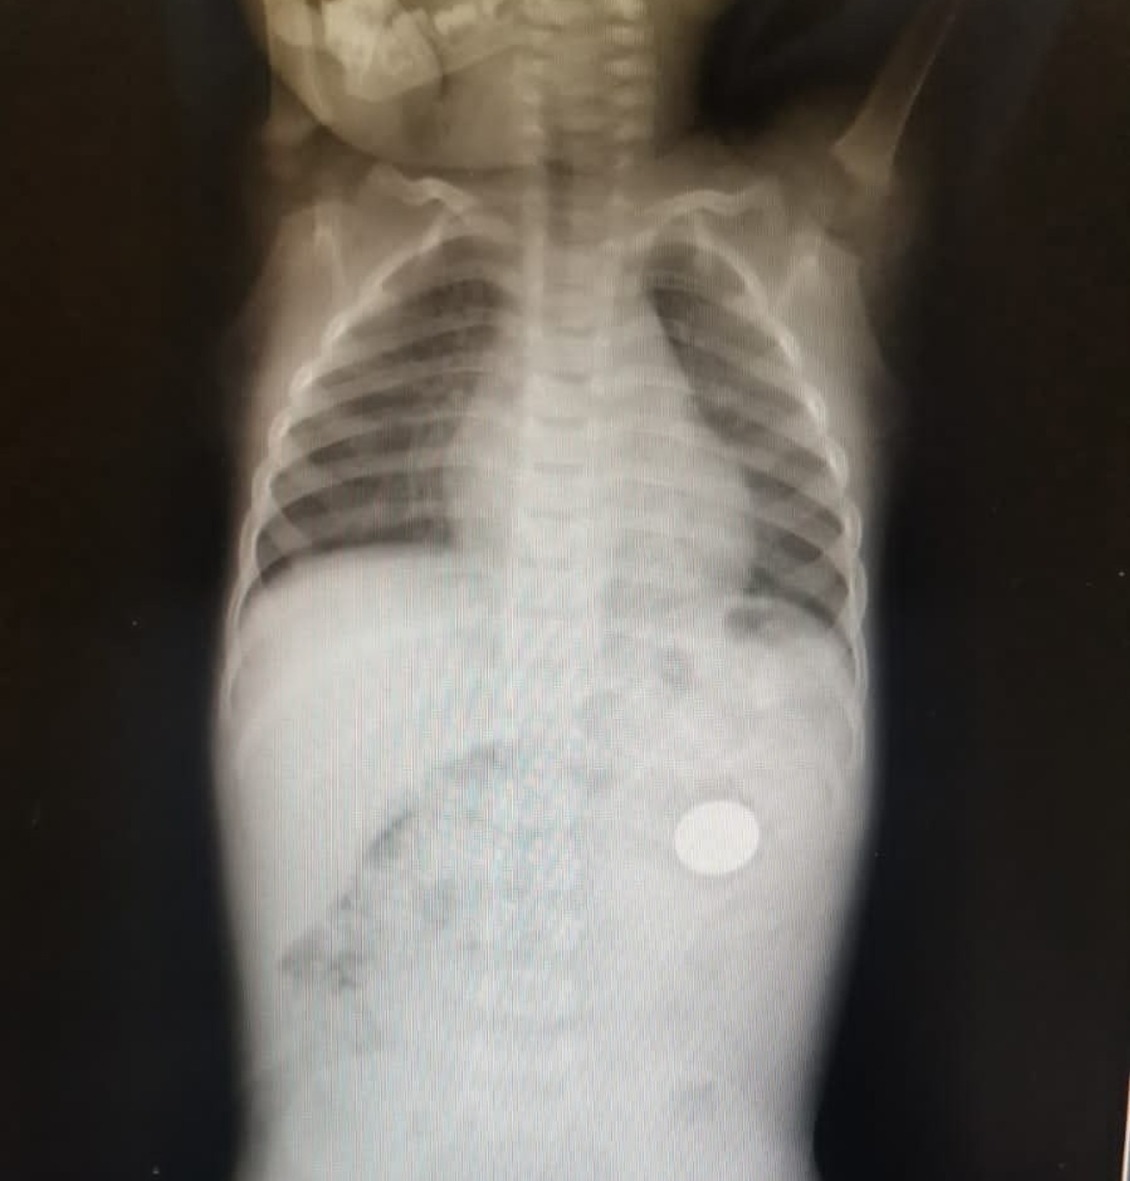

В июне в детское хирургическое отделение клинической больницы станции скорой медицинской помощи Уфы доставили трехлетнего малыша. Родители сообщили, что дядя, нумизмат, дал ребенку поиграть с экземпляром из своей коллекции. Рентген показал, что инородное тело застряло в пищеводе у ребенка. Детские хирурги успешно удалили монету иностранного происхождения.